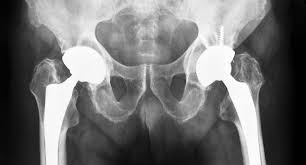

Several hip conditions lead patients toward precision hip replacement. Osteoarthritis causes cartilage wear and joint stiffness. Similarly, avascular necrosis weakens bone due to poor blood supply. Hip injuries, fractures, and deformities also disrupt joint mechanics. Doctors recommend surgery when pain limits daily activity and reduces quality of life. Early precision-based intervention prevents further damage and improves long-term joint performance.

Precision hip replacement depends heavily on detailed pre-surgical planning. Doctors analyze imaging studies and movement patterns to understand joint mechanics clearly. This process helps determine the ideal implant size, position, and alignment.

Precision hip replacement offers lasting pain relief and improved joint performance. Accurate alignment enhances stability and reduces implant wear. Patients notice smoother movement and better posture. With proper rehabilitation and follow-up care, patients maintain hip function for many years. This improvement allows a more active and independent lifestyle.

Long-term success depends on maintaining healthy habits after surgery. Patients should follow physiotherapy instructions and stay physically active within recommended limits. Low-impact exercises help strengthen muscles and protect the joint. Maintaining a healthy weight reduces stress on the hip implant. Regular follow-ups ensure continued joint health and early detection of concerns.